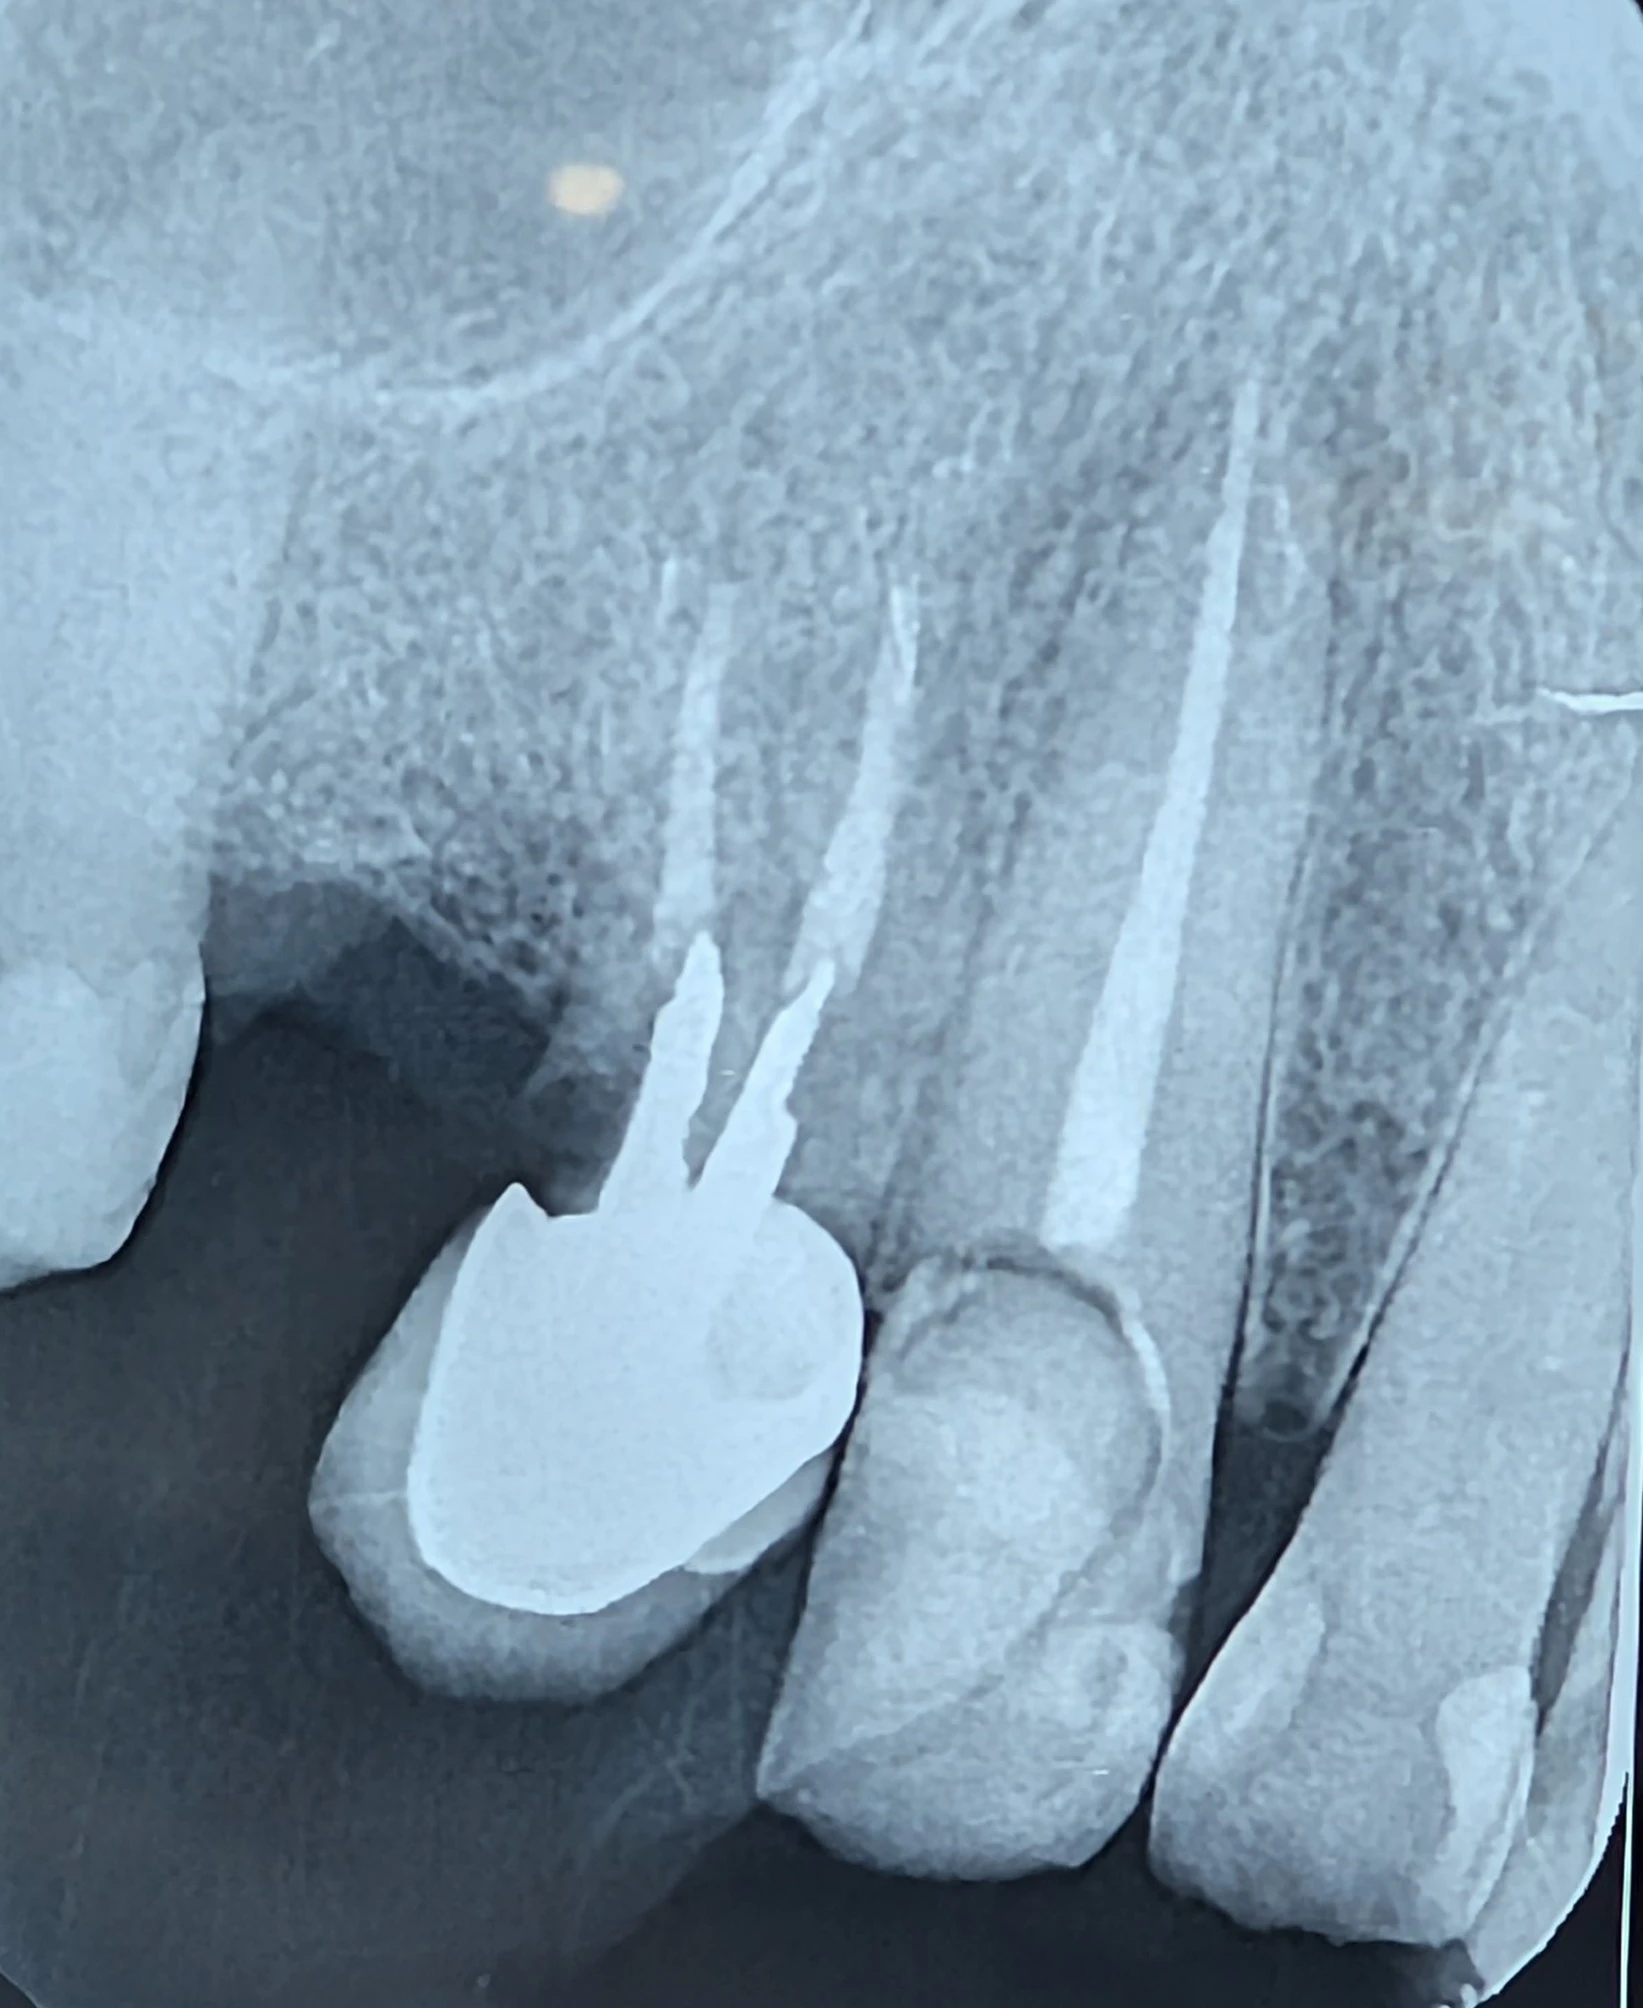

بیمار با نیاز به ایمپلنت برای نواحی ۴ و ۵ مراجعه کرده بود. دندان ۳ بهتازگی درمان ریشه شده بود و بیمار انتظار داشت روی همین دندان نیز روکش قرار بگیرد.

در ارزیابی رادیوگرافی و کلینیکی مشخص شد:

- فرول پالاتال وجود ندارد (عامل حیاتی در کانین بالا).

- فرول مزیال نیز از بین رفته است.

- موقعیت دندان کانین بهگونهای است که همیشه تحت فشارهای لترال شدید قرار دارد.

در ظاهر، میشد این دندان را نگه داشت، پستوکور گذاشت و روکش کرد. اما این فقط «نگاه به امروز» بود.

در ارزیابی تیمی با متخصص لثه، مشخص شد ایجاد فرول پالاتال:

- نیازمند برداشت وسیع استخوان است،

- آیندهٔ پریودنتال را ضعیف میکند،

- و حتی با بهترین کار ترمیمی، بیومکانیک دندان قابل اعتماد نخواهد بود.